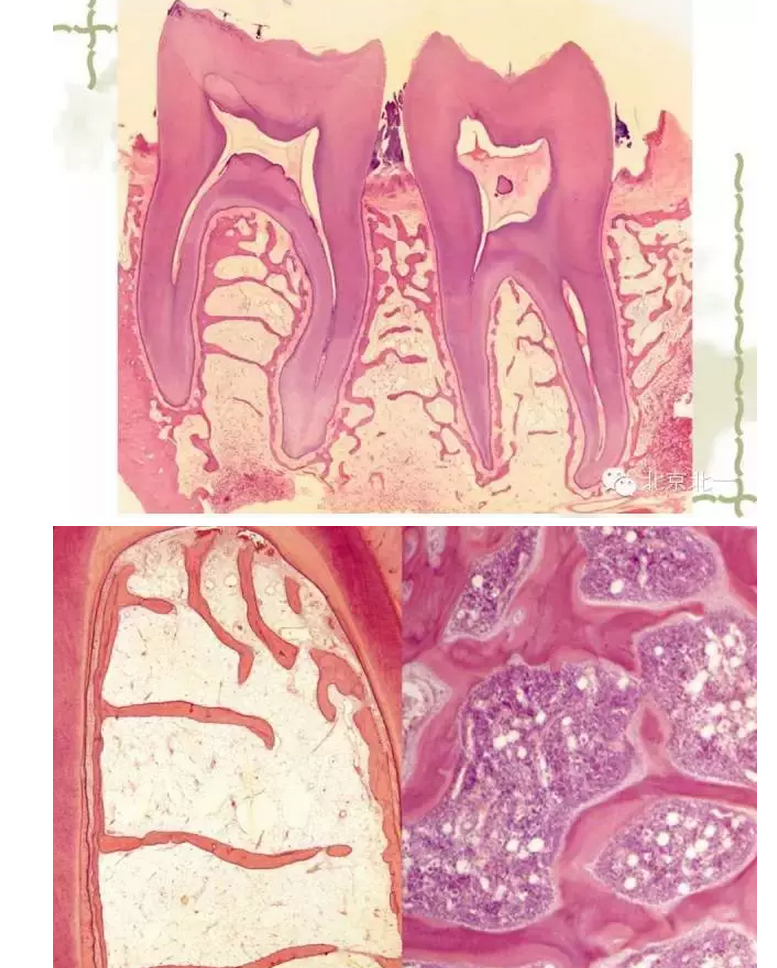

【牙周學(xué)習(xí)】牙周組織--基礎(chǔ)知識(shí)篇(下)